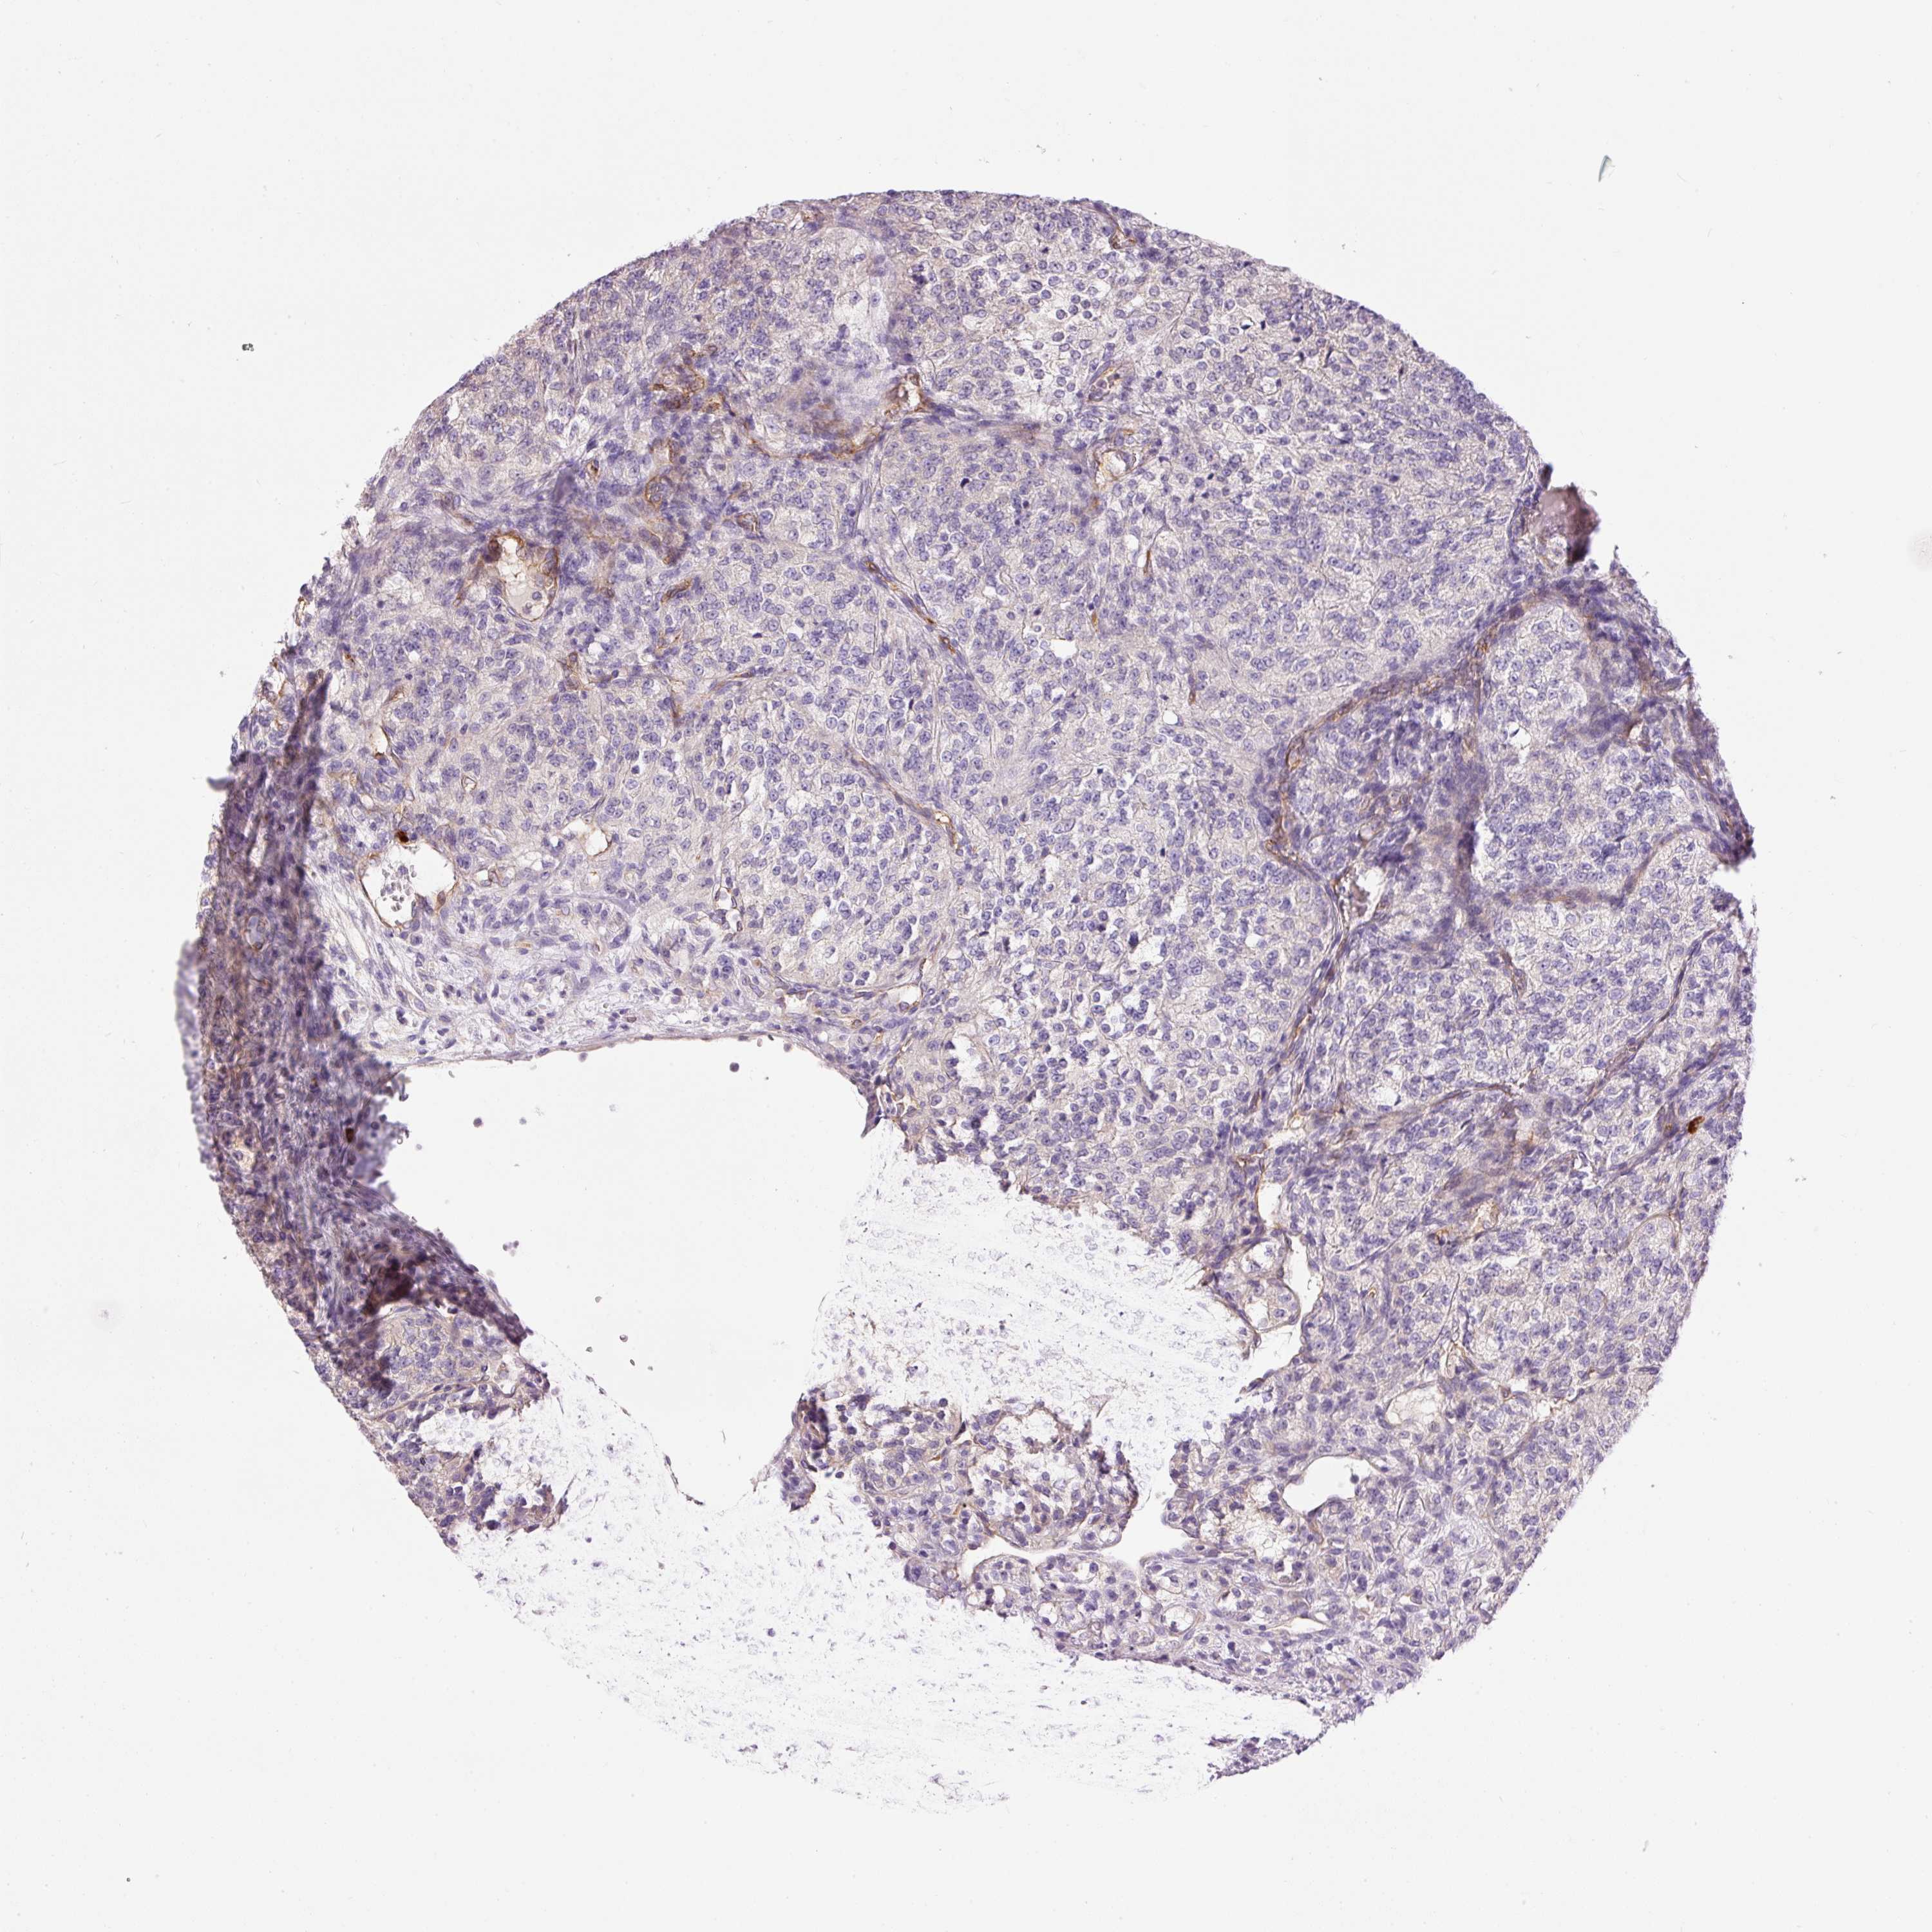

KIDNEY RENAL PAPILLARY CELL CARCINOMA (TCGA) - Interactive survival scatter ploti

The Survival Scatter plot shows the clinical status (i.e. dead or alive) for all individuals in the patient cohort, based on the same data that underlies the corresponding Kaplan-Meier plots. Patients that are alive at last time for follow-up are shown in blue and patients who have died during the study are shown in red.

The x-axis shows the expression levels (FPKM) of the investigated gene in the tumor tissue at the time of diagnosis. The y-axis shows the follow-up time after diagnosis (years). Both axes are complimented with kernel density curves demonstrating the data density over the axes. The top density plot shows the expression levels (FPKM) distribution among dead (red) and alive patients (blue). The right density plot shows the data density of the survived years of dead patients with high and low expression levels respectively, stratified using the cutoff indicated by the vertical dashed line through the Survival Scatter plot. This cutoff is automatically defined based on the FPKM cutoff that minimizes the p-score. The cutoff can be changed by dragging the vertical line or by entering a cutoff value in the square labeled "Current cut-off".

Under the Survival Scatter plot the p-score landscape (black curve; left axis) is shown together with dead median separation (red curve; right axis). Dead median separation is the difference in median mRNA expression between patients who have died with high and low expression, respectively. It is calculated as follows: median FPKM expression of dead patients with high expression - median FPKM expression of dead patients with low expression. This is intended to aid the user in visually exploring custom cutoffs and the associated p-scores and dead median separation.

Individual patient data is displayed and can be filtered by clicking on one or more of the category buttons on the top of the page. Categories describing expression level and patient information include: high, low, alive, dead, female, male and tumor stages. The scale of the x-axis can be toggled between linear and log-scale by clicking on the "x log" button. Mouse-over function shows TCGA ID, patient information and mRNA expression (FPKM) for each patient.

& Survival analysisi

Kaplan-Meier plots summarize results from analysis of correlation between mRNA expression level and patient survival. Patients were divided based on level of expression into one of the two groups "low" (under cut off) or "high" (over cut off). X-axis shows time for survival (years) and y-axis shows the probability of survival, where 1.0 corresponds to 100 percent.

PNPLA5 is not prognostic in Kidney Renal Papillary Cell Carcinoma (TCGA)